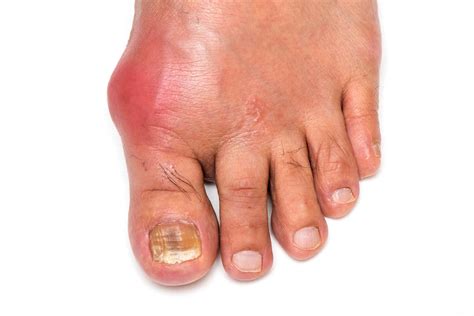

• Swelling and Inflammation: The area around the MTP joint may look red, swollen, and tender to the touch.

• Bone Spurs (Osteophytes): As the cartilage erodes, the body attempts to repair the joint by forming bone spurs on the top of the toe. These can create a noticeable bump that rubs against your footwear.

⚠️ Note: If you notice sudden, severe pain, redness, or heat, it may be a sign of gout or an infection rather than standard wear-and-tear arthritis. Consult a medical professional immediately if you experience these acute symptoms.